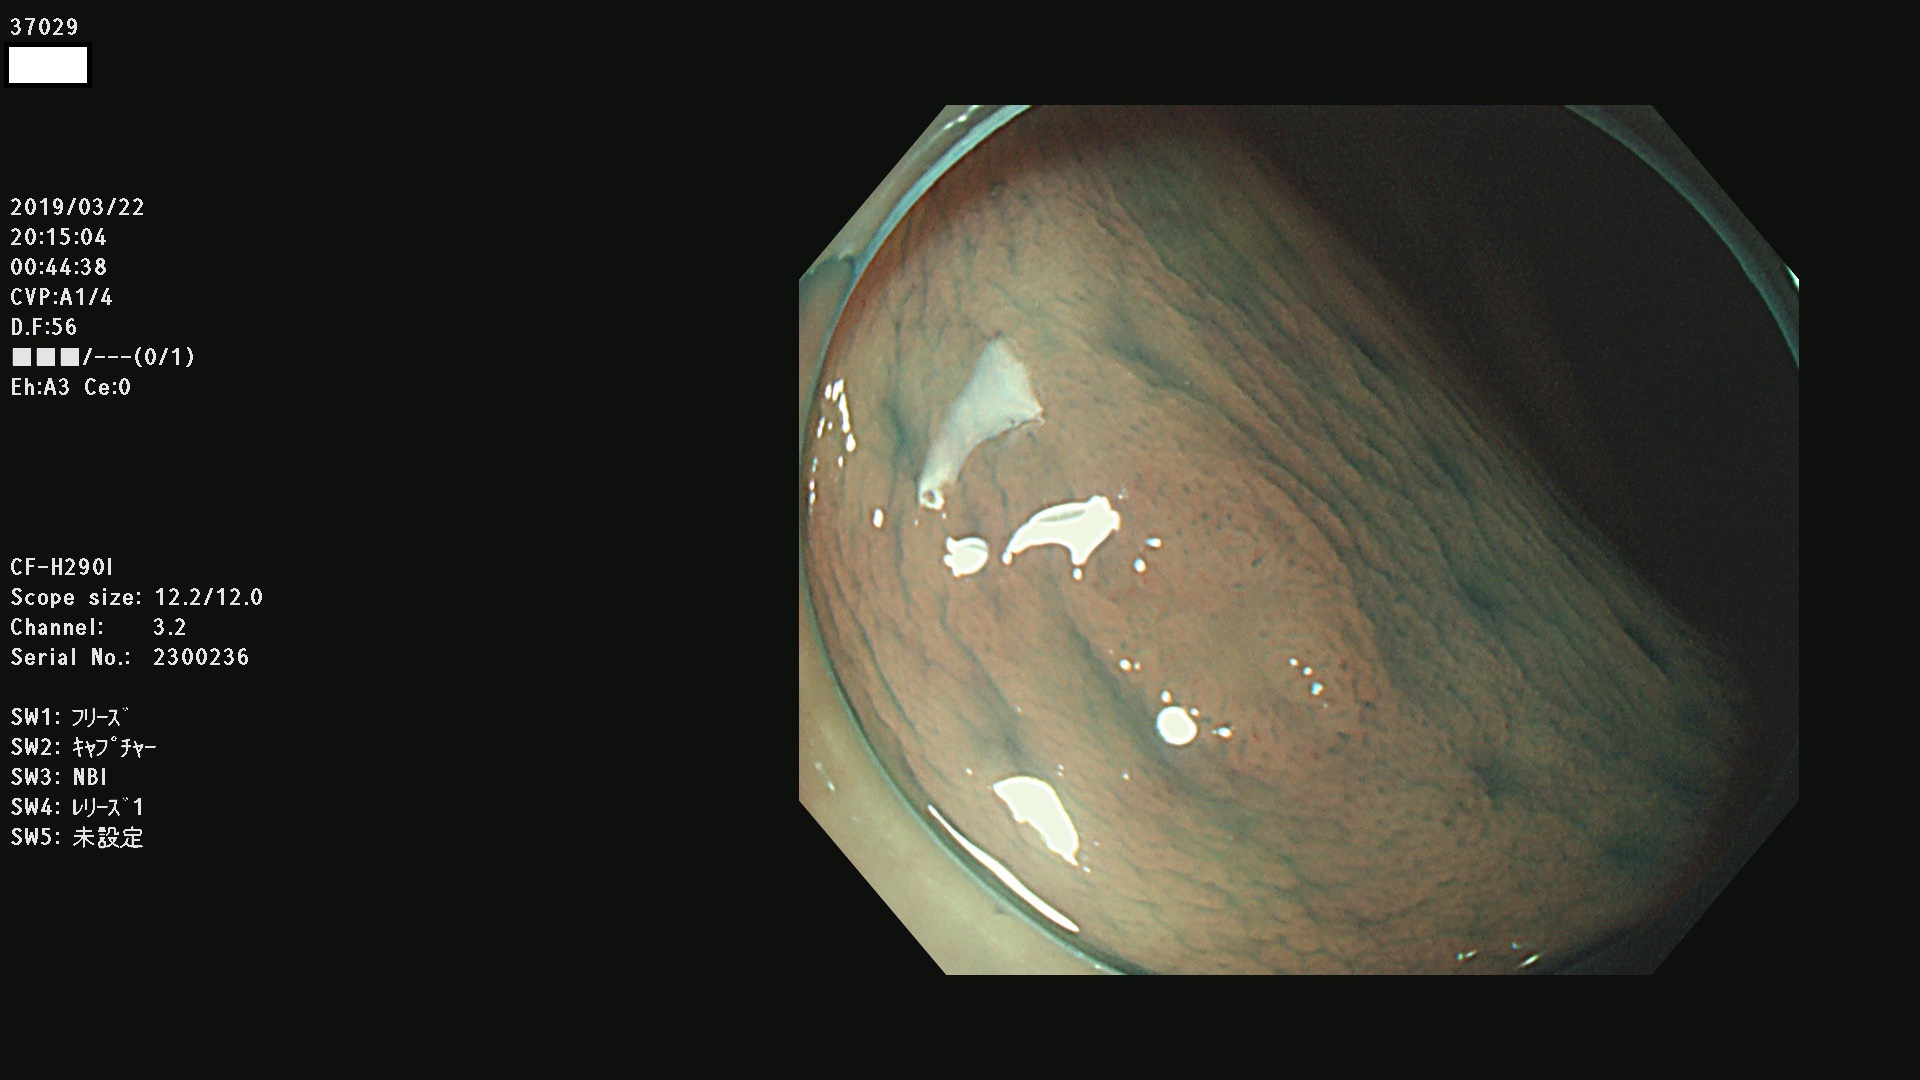

37000 37002 37004 37005 37006(SSAPのみ) 37007 37009 37013 37014 37015 37017(SSAPのみ) 37019 37020 37021 37022 37025 37026 37027 37028 37029 37031 37032 37033 37034 37035 37036 37037 37038 37041 37042 37043 37044 37045 37047 37051 37052 37053(SSAPのみ) 37055 37056 37058 37060 37061 37062 37063 37067 37072 37073 37074 37076 37077 37078 37079 37080 37081 37083 37084 37085(SSAPのみ) 37086 37087 37088 37089 37092 37093 37094 37095 37097 37098 3709

発見困難で危険性の高い平坦型病変(上記100名より抽出)